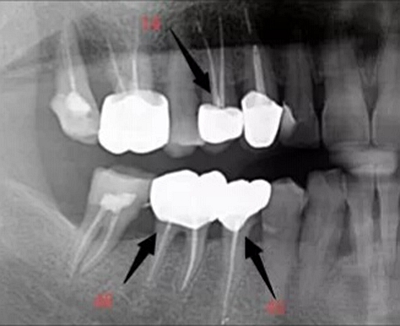

1.根管引導(dǎo)劑:新的根管引導(dǎo)劑,能快速溶解細小閉鎖根管口,溶解潤滑根管壁,使根管擴大器械安全,快速到達根尖位置。

2.半導(dǎo)體激光加碘仿液,高效殺死根管和側(cè)付根管內(nèi)感染細菌,激光根管及牙周綜合完善消毒,光照點約600~800度瞬間高溫使根管內(nèi)感染組織、蛋白質(zhì)、細菌、血液殘留和碘仿液瞬間氣化,達到快速滅菌效果。

3.定向骨誘導(dǎo)劑的使用,使生物牙產(chǎn)生骨結(jié)合,增強了患牙穩(wěn)固度,提高了咬合力。

4.3D液體牙膠充填劑,可以有效到達根尖部及側(cè)付根管,使根管內(nèi)不留死腔,有效封閉側(cè)付根管和根尖孔,提高了治愈率。

5.激光+根管及主要側(cè)副根管的均質(zhì)3D充填+定向骨誘導(dǎo)結(jié)合,徹底解決了擴大(原來難找、難擴)、消毒(原來有效率<80%)及骨結(jié)合問題,使牙髓及牙周得到了比傳統(tǒng)方法更有效的治療。